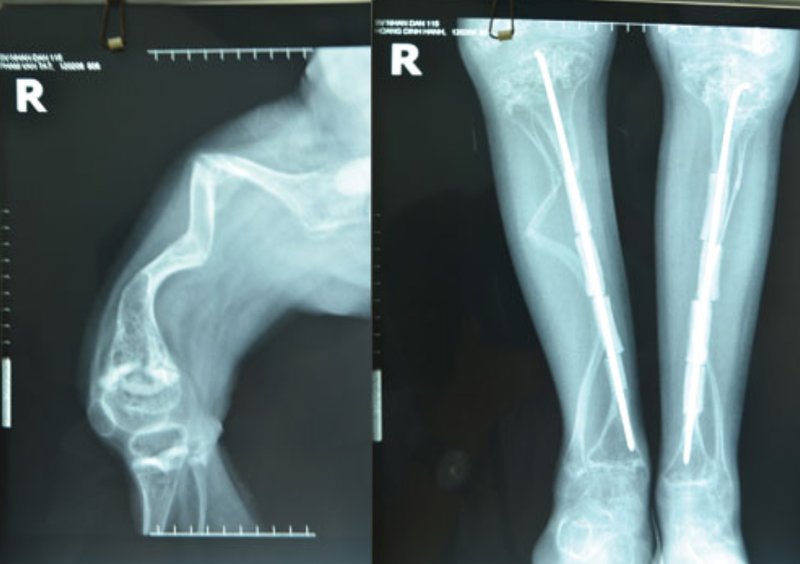

/https://cms-prod.s3-sgn09.fptcloud.com/nhan_biet_benh_xuong_thuy_tinh_o_tre_2_e13f3cfc82.png) Những xét nghiệm X-quang cho thấy trẻ mắc bệnh xương thủy tinh có xương tứ chi biến dạng

Những xét nghiệm X-quang cho thấy trẻ mắc bệnh xương thủy tinh có xương tứ chi biến dạngXương thủy tinh 3: Là thể tương đối nặng, nguyên nhân là do tình trạng suy giảm chất lượng xương do thiếu hụt hàm lượng collagen và mô liên kết ở mức độ tương đối nặng, khiến xương của trẻ trở nên giòn và giảm khả năng chịu lực.

Chế độ dinh dưỡng để cơ thể tăng tổng hợp collagen và canxi giúp trẻ khỏe xươngXương thủy tinh là một trong những căn bệnh không thể phòng ngừa được do trẻ mắc bệnh từ khi còn trong bụng mẹ. Những xét nghiệm X-quang cho thấy tình trạng trẻ mắc bệnh xương thủy tinh có xương tứ chi biến dạng, vỏ xương mỏng, giảm độ đặc của xương. Vì thế khi trẻ được chẩn đoán mắc bệnh này, tùy vào mức độ của xương mà bác sĩ sẽ xác định được các dạng tuýp của xương thủy tinh. Nếu bác sĩ chỉ định bé có thể sinh ra bình thường thì mẹ nên chăm sóc trẻ theo chế độ đặc biệt hơn.